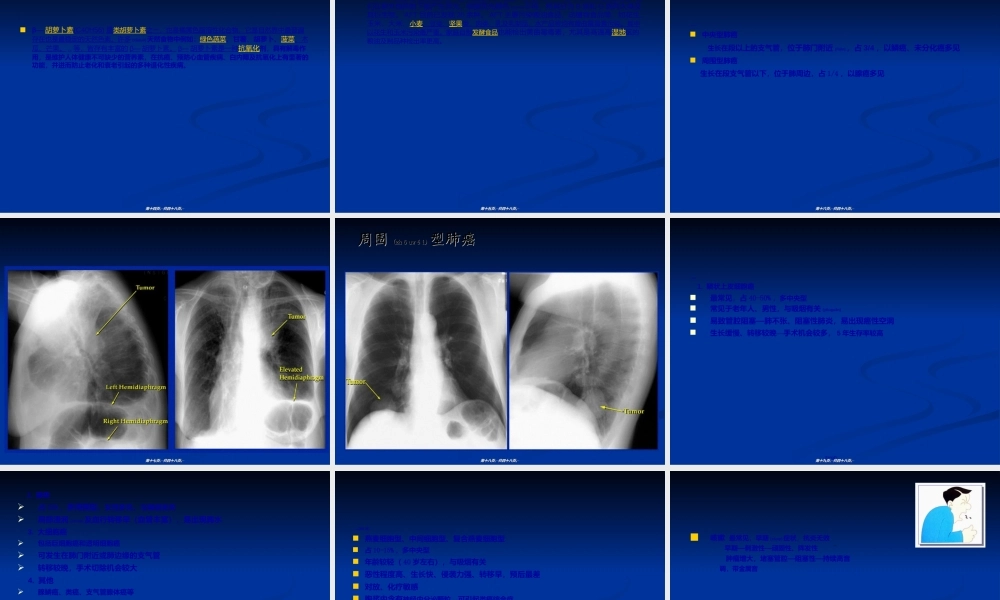

原发性支气管肺癌原发性支气管肺癌(fèi(fèiái)ái)((PrimaryBronchogenicPrimaryBronchogenicCarcinomaCarcinoma))第一页,共四十八页。第一页,共四十八页。了解原发性支气管肺癌的概念、病因(bìngyīn)及发病机制。熟悉原发性支气管肺癌的临床表现、相关检查及治疗原则。第二页,共四十八页。第二页,共四十八页。简称肺癌(lungcancer),肿瘤细胞起源于支气管粘膜或腺体,常有区域性淋巴结转移和血行播散。早期常有刺激性咳嗽,痰中带血等呼吸道症状(zhèngzhuàng),病情进展速度与细胞生物特性有关第三页,共四十八页。第三页,共四十八页。为最常见的恶性肿瘤之一,半个世纪来发病率、死亡率都明显增高1999年统计,肺癌居癌症死因第一位(WHO)尽管目前肺癌的早期诊断(zhěnduàn)和综合治疗有了较大进展,但其5年生存率仍低于15%第四页,共四十八页。第四页,共四十八页。第五页,共四十八页。第五页,共四十八页。第六页,共四十八页。第六页,共四十八页。近20年来,我国的肺癌发病率以每年(měinián)11%的速度递增,死亡率增幅111.85%肺癌在城市已跃居癌症死亡首位(男性首位,女性仅次于乳腺癌)死死亡亡率率7070年代年代(niándài)(niándài)9090年代年代(niándài)(niándài)7.17/107.17/10万人万人15.9/1015.9/10万人万人第七页,共四十八页。第七页,共四十八页。1、吸烟是公认的肺癌危险因素。烟雾中含20多种致癌物(苯并<或a>芘)吸烟者肺癌发生率比非吸烟者高10-20倍,死亡率高10-30倍(被动吸烟者危险性增加(zēngjiā)50%)国内资料:男性肺癌85-90%,女性19.3-40%与吸烟有关吸烟量越大、年限越长、吸烟年龄开始越早,肺癌死亡率越高第八页,共四十八页。第八页,共四十八页。2、职业致癌因子已知石棉、煤焦油、沥青、石油、无机砷、烟草(yāncǎo)加热产物、铬、镍、芥子气等与肺癌有关石棉工人肺癌发生率高8倍(吸烟者)、92倍(非吸烟者)云南锡矿(含氡)的井下工比地面职工高23-98倍第九页,共四十八页。第九页,共四十八页。第十页,共四十八页。第十页,共四十八页。3、空气污染室内小环境:被动吸烟、燃料燃烧和烹调(pēngtiáo)过程中产生的致癌物室外大环境:汽车废气、工业废气、公路沥青等污染肺癌发病率:城市高于农村,大城市高于中、小城市4、电离辐射自然界、医疗、工矿产生的辐射线第十一页,共四十八页。第十一页,共四十八页。5、饮食与营养维生素A及...